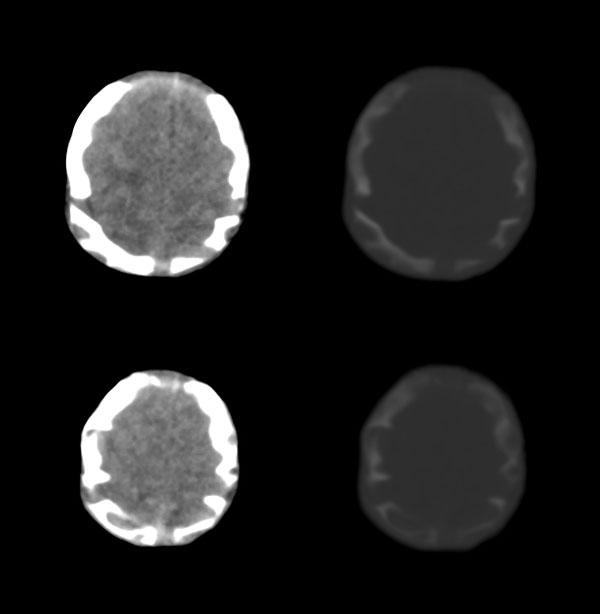

2天,枕部肿物

枕骨缺损,脑膜脑膨出。同时第4脑室挤压变形、闭塞,致使第3脑室、双侧侧脑室显著积水、扩张,过高的颅内压推挤脑实质,致使颅骨内板出现多而且深的脑回样压迹,脑细胞水肿,皮质、白质分界不清。

考虑先天性中脑水管梗阻,其以上脑室扩大。枕部脑膜脑膨出!

枕骨脑裂畸形伴脑膜脑膨出,双侧脑室扩张积水,第四脑室变窄致使双侧侧脑室及第三脑室积水,

枕骨缺损,脑膜脑膨出。同时第4脑室挤压变形、闭塞,致使第3脑室、双侧侧脑室显著积水、扩张.

脑积水——第4脑室挤压变形、闭塞,致使第3脑室、双侧侧脑室显著积水、扩张

颅骨内面凹陷——过高的颅内压推挤脑实质,过高的颅内压推挤脑实质,致使颅骨内板出现多而且深的脑回样压迹